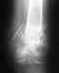

05.03.2013 года моей супруге провели операцию с диагнозом перелом голени со смещением, была вставлена спица. 11.03.2013 года забрал супругу домой.

Вообще, ситуация без снимков непонятная. Куда и зачем была вставлена какая спица при каком переломе костей голени - можно только гадать.